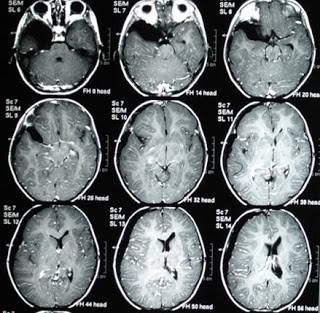

(FOTO: Ilustrativa)